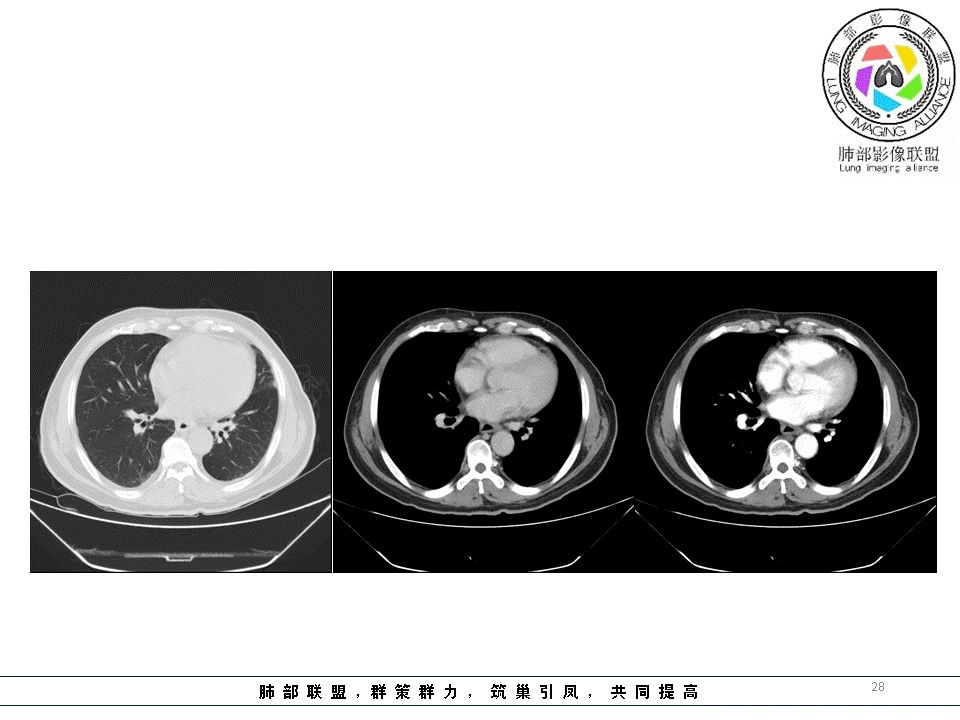

结果

结果:肺腺癌并纵膈淋巴结转移

编后的话:

1.临床实践中我们可能会有过多次这样的经验,右锁骨上淋巴结病理肺腺癌,但未能明确原发病灶之所在。该例也是如此,也许在肺叶中瞒天过海,也许隐匿肺门结构间。

2.鳞癌转移迟,左侧支气管腔内阴影多次取材应当能够排除发生于腔内的鳞癌。况患者未引发阻塞性改变。

3.肺癌淋巴结转移多有一定规律可循。右肺病灶均沿右肺血管束、右肺门、右侧纵隔上行;左肺下叶病灶沿左下肺血管束、左肺门、隆凸及右侧纵隔上行;左肺上叶病灶沿左上肺血管束、左肺门、主动脉窗及左侧纵隔上行。

该例左肺门及腔静脉后淋巴结肿大,是符合这规律的。

4.结节病偏偏双肺门淋巴结增大为主要特点,淋巴结密实且密度偏高。

5.淋巴瘤则主要位于前上纵膈,多发,密度较均匀一致,大小相仿,且无左右之分。